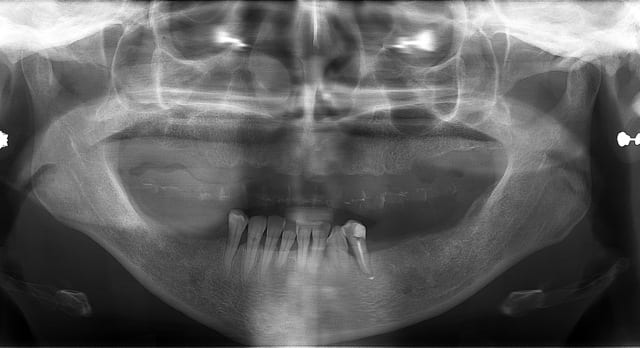

pour la petite histoire, la patient dépressive est venue il y a 4 ans pour la première fois.

ses dents étaient mobiles, elle était complexée, gardait souvent la mains devant la bouche quand elle parlait...

j'ai mis deux ans à la décider à sauter le pas et faire extraire ce qui lui restait en haut pour lui poser une PAC.

et encore 1 an et demi pour la décider à passer aux implants.

comme on peut le voir sur les premières photos, la forme des gencives était magnifique, si seulement j'avais pu poser des implants à ce moment là et profiter des papilles résiduelles que lui avait laissé son stellite...

1 opt d part xjckyt - Eugenol

2 opt 3ans apr s hb4fth - Eugenol